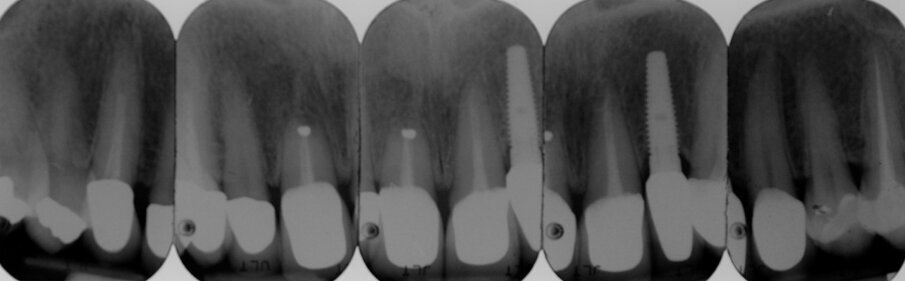

Le radiografie del caso completato nell’inizio del 2010 (Fig. 4) evidenziano la precisione del lavoro che è poi stato mantenuto nel corso degli anni. L’incisivo centrale destro 11 era stato trattato con apicectomia in passato ed era l’unico dente non vitale della riabilitazione. La paziente era seguita dal protesista che aveva portato a termine il caso. Nel 2021 la signora si è ripresentata con sintomatologia sul dente 21. Il lavoro eseguito nel 2010 era ancora in buone condizioni fatta eccezione per 11-12 ove 12 presentava una recessione gengivale con esposizione del collarino della cappetta galvanica che supportava la corona in ceramica e 11 presentava una piccola fistola nella sua porzione vestibolo distale (Figg. 5-7). La diagnosi era abbastanza semplice, l’11 aveva una frattura verticale e una prognosi infausta.